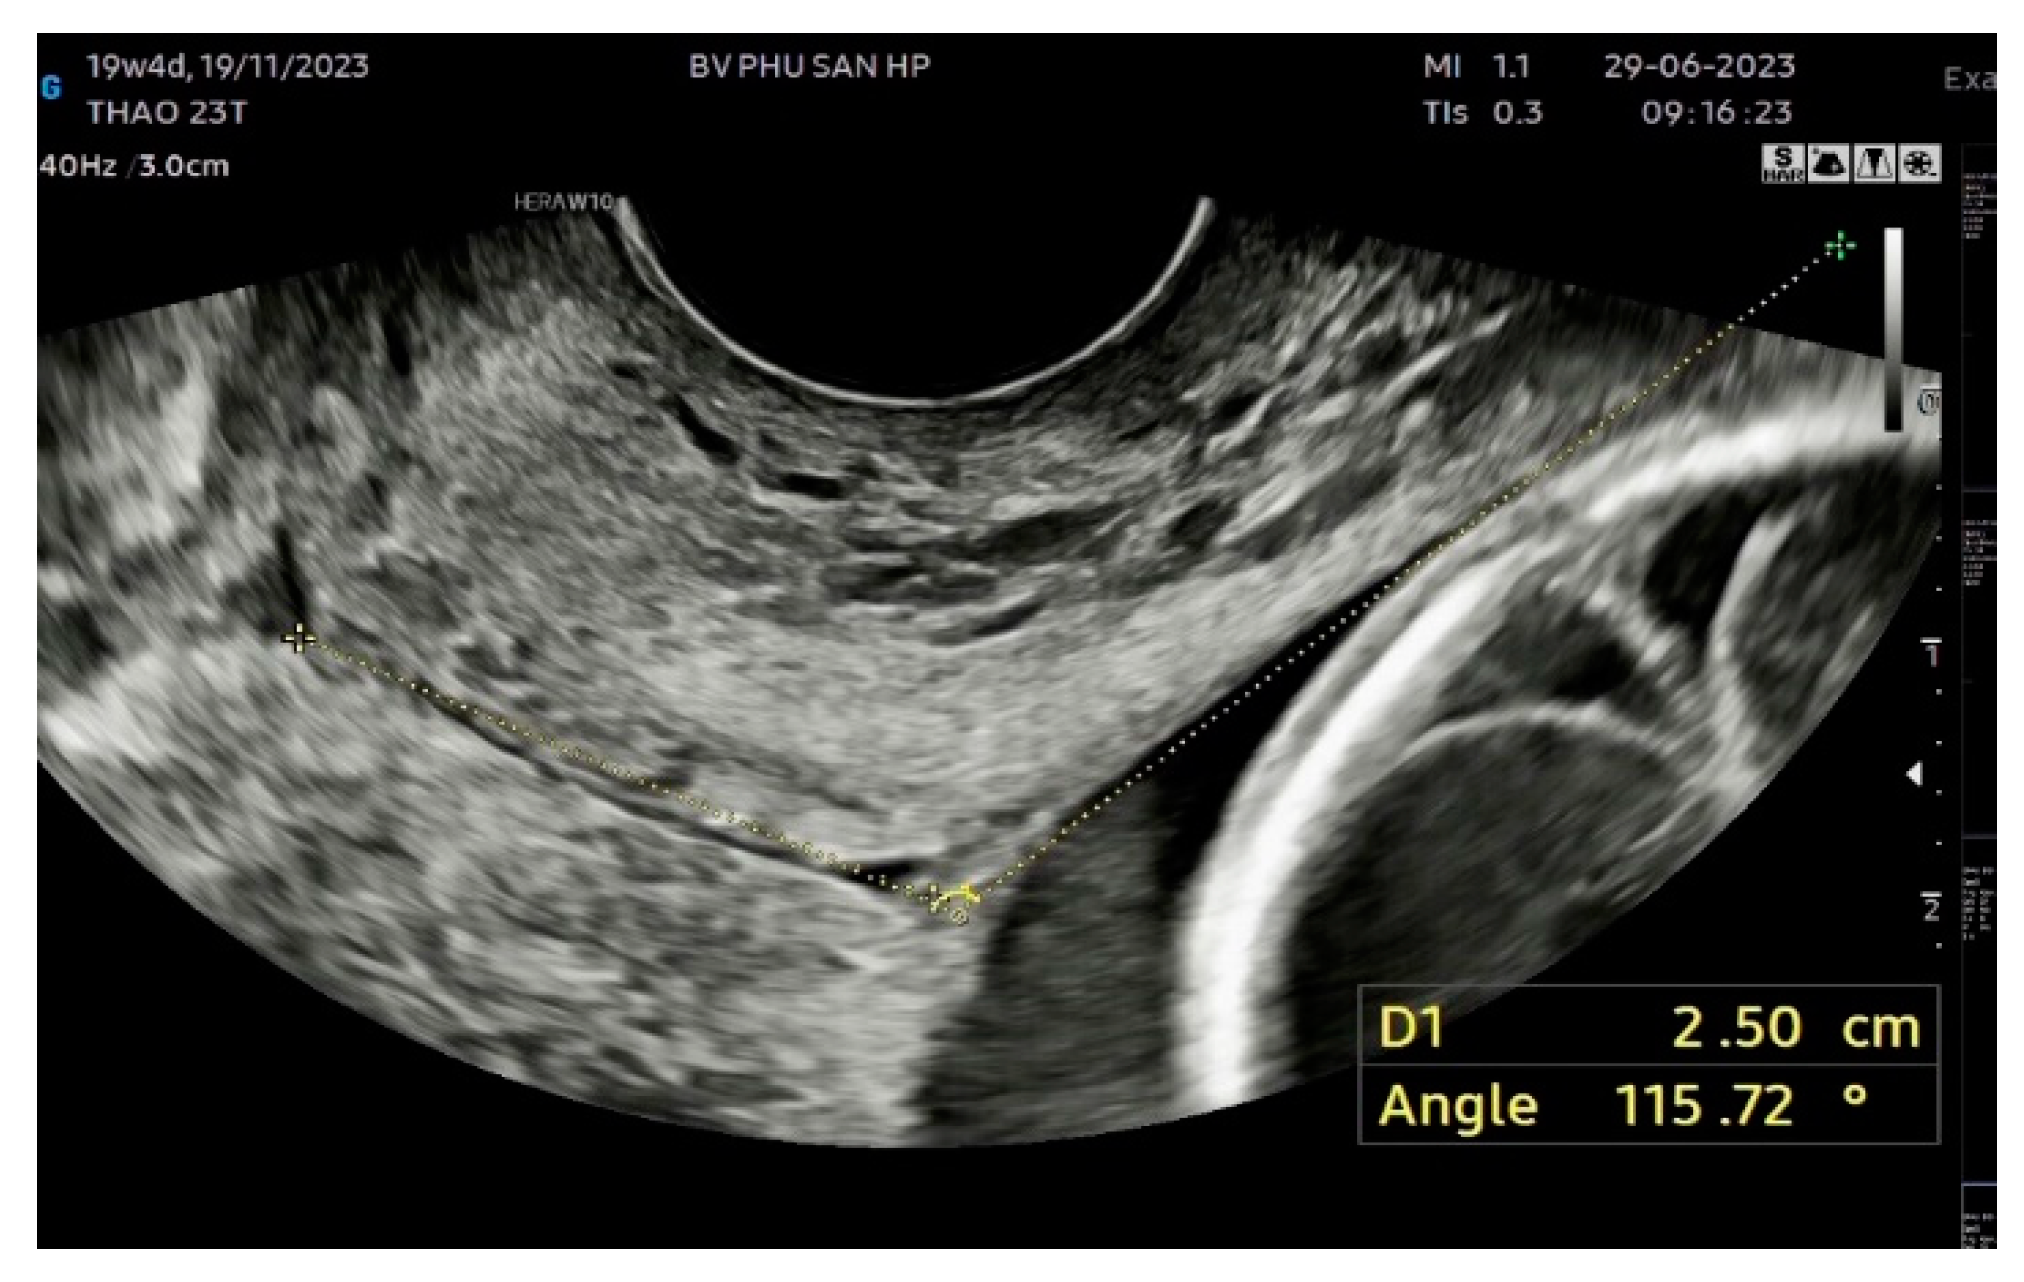

The UCA was measured according to the method described by Dziadosz et al. [14]. The UCA was calculated as the angle between two lines. The first line was drawn between the internal (I) and external ostium (os) (E). The second line was drawn 3 cm parallel to the lower aspect of the anterior inner uterine wall passing through the end of the first line at the internal os (Figure 2). Each participant had three images measured to reduce measurement bias, and the most obtuse UCA from the three images was used.

Figure 2. Transvaginal sonographic images showing the measurement technique of UCA at 19+4 weeks of gestation with a CL of 25 mm and UCA of 115.72o.